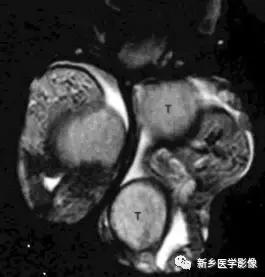

(二十)多睾

是用在生殖器形成(宫内发育6-8周)期间生殖嵴分裂导致一个或多个额外*丸睾**发育的罕见疾病。左侧多见,也可以双侧受累,多数额外*丸睾**位于阴囊内,少数位于腹股沟或腹膜后。额外*丸睾**体积相对小,可共享附睾和导管,或者缺如